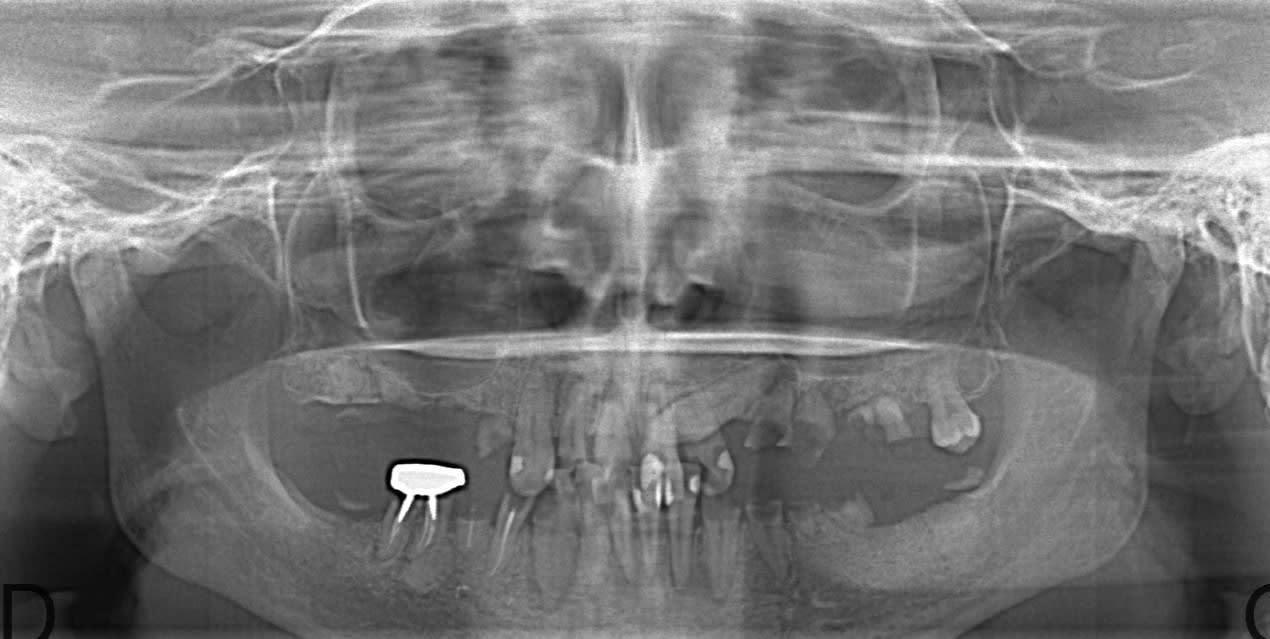

Je vous mets la pano ... avec des surprises . On vire tout , ou presque ?

Je ferais mon maximum pour conserver 33 et 43 pour placer un partiel en bas et un complet en ht.